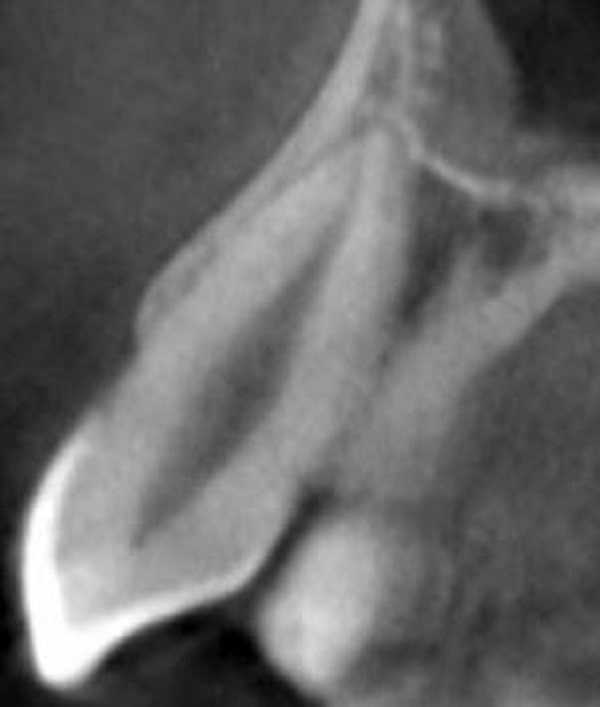

In the present study, the most common root canal pattern in the maxillary canine was a Type I in 100% of the samples (Figure 1). Similar findings were reported by Pineda and Kuttler (100%) (15), Vertucci (100%) (18), and Mağat (0,1%) (23) but the prevalence of an additional canal in maxillary canines, in this study, was lower than Amardeep et al. (20,4%) (5), Çalışkan et al. (6,52%) (19), Sert and Bayırlı (6,5%) (20), Altunsoy (female 1,3%, male 3,2%) (21), and Büyükbayram et al. (2,44%) (25), in maxillary canines (Table 5). The difference in the findings of the other authors may be explained by study techniques, number of patients, the number of teeth and different populations.